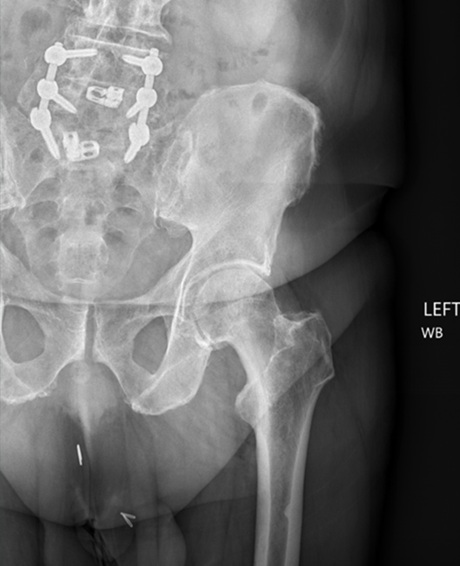

His radiographs in the clinic revealed left hip degenerative joint disease. Additionally, his pre-operative hip MRI revealed significant narrowing of the joint space and femoral head edema securing the diagnosis of degenerative joint disease. His exam was significant for limited internal rotation to no more than 5 degrees, a positive stinchfield test and an antalgic gait.

Radiographs are noted below. Pre-op, Post-op and intra-op radiographs are found below as well as the pre-op MRI.

Figures 1, 2 and 3. AP of the Pelvis, AP of the Left Hip, and a Frog Leg Lateral of the Left Hip demonstrating left hip osteoarthritis.

Figure 2.